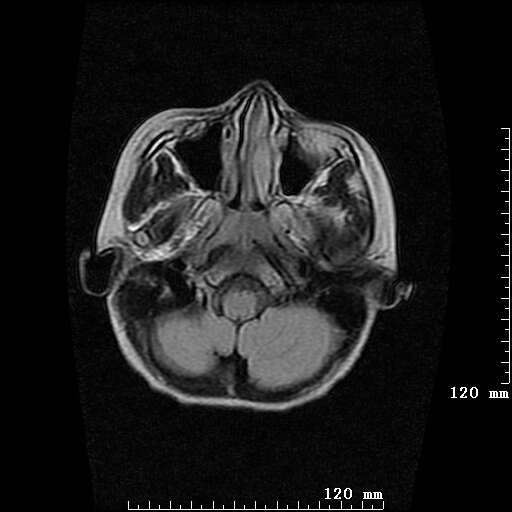

女,7岁,三岁才说话、走路。现智力尚可,走路不稳。临床怀疑大脑发育不全。

脑裂畸形伴灰质异位

只看出灰质异位